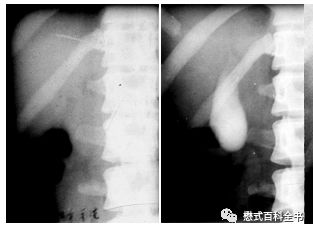

图1:ERCP示意图

和MRCP类似的一个单词叫做ERCP(Endoscopic Retrograde CholangioPancreatography),翻译过来就是(经内镜)逆行性胰胆管造影术。Endo-是内、在内的前缀,-scopic表示观测、观察,当然endoscopic这个词本来就是内窥镜的,用内镜的方式的意思。Retro-是一个使用比较多的前缀,代表向后的,回顾的,*退倒**的。大家还记得我们的回顾性心电门控是怎么表述的吗?Retrospective,回顾性研究,回顾性分析都是这个前缀。grade这个单词大家熟悉,可以理解为年级、级别、阶段。

retrograde就很好理解了,为了信达雅和结合技术把它翻译为逆行性的。而同样的单词cholangiopancreatography在MRCP中翻译为成像,在ERCP中翻译为造影术更恰当。因为ERCP是一种有创性的手术方式,并且会注入造影剂以使胆囊及胆管系统显影,所以用造影术是比较合适的。

图2、3:ERCP图像